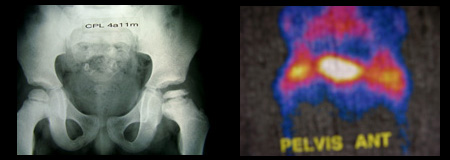

Que hace el Ortopedista Pediatra?  Cuando un niño acude a la consulta por tener dolor o cojear  se solicita una placa Radiográfica. En la fase de  necrosis  o en las siguiente, por lo general el Ortopedista Pediatra hace el diagnostico en base a placas de cadera, pero en  la etapa muy inicial ( sinovitica), estas placas pueden ser normales  u observarse en ocasiones datos tempranos  muy sutiles de la enfermedad como es una disminución en la altura de la cabeza femoral. Cuando se tiene sospecha de la enfermedad antes de que haya cambios radiográficos es muy útil solicitar un estudio de Resonancia Magnética  y de Gammagrafía Ósea. Existen otras enfermedades que puede, dar una apariencia radiográfica semejante al Perthes como es el caso de paciente con Hipotiroidismo o Displasia Epifisiaria.

4.-  Los rayos equis muestra afectación parcial o total de la cabeza del fémur?  , a mayor afectación pronostico menos bueno. Se observa en la placa radiográfica una cabeza femoral bien contenida en el Acetábulo?, el pronóstico será mejor.